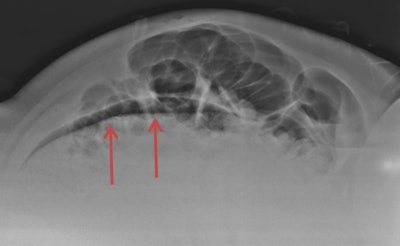

Cross-table lateral radiograph of the abdomen. Evidence of a translucent image was not correctly interpreted as pneumoperitoneum. Image courtesy of Dr. Antonio Pinto.However, there is a high risk of malpractice claims in view of the need for a rapid diagnosis and the management of patients with whom radiologists have had no prior interaction and who, quite often, may be uncooperative or under the influence of drugs or alcohol.

The imaging workup of patients with abdominal pain often starts with supine and upright abdominal x-rays and upright chest x-ray, and it is misinterpreting these images that is the main cause of diagnostic error in the emergency department, according to Pinto. He pointed to other factors contributing to missed diagnoses, such as a lack of relevant clinical information, inappropriate or insufficient x-rays, failure to perceive signs, and lack of knowledge.